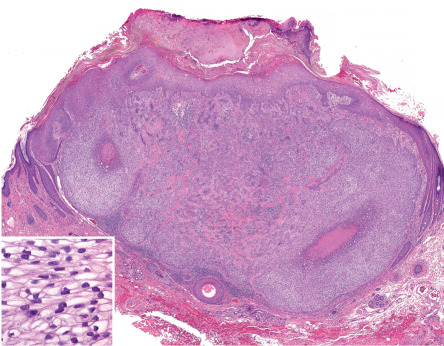

Pathology

All trichoepitheliomas and trichoblastomas have in common the architectural attributes of a benign neoplasm – namely, relative symmetry, circumscription, and a lack of substantial cytologic atypicality. In addition, all are linked by prominence of follicular germinative cells with enveloping fibrocytic stroma that varies in degree . In classic trichoepithelioma, the fibrocytic stroma is conspicuous and constitutes as much as half of the cellularity of the lesion in a given cross-section. In other lesions that simulate BCC, follicular germinative cells may be arrayed as either small or large nodules with only scant intervening sclerotic stroma. The coarse fibrous stroma typically maintains tightly adherent contact to the lesional follicular germinative cells . This is in distinct contrast to the pattern of BCC, in which clefts between basaloid cells and stromal elements often serve as a diagnostic clue.

In classic trichoepithelioma, follicular germinative cells are often disposed as small clusters or as reticulate and cribriform cords ( Fig. 111.13 ). There are usually foci of pronounced bulbar differentiation, emulating the follicular bulb and papilla; these structures have been termed papillary mesenchymal bodies . Classic trichoepithelioma does not typically show follicular germinative differentiation exclusively. Rather, small cornifying cystic spaces with surrounding pinkish keratinocytes, reflecting concurrent infundibular or isthmic differentiation, are also apparent.

In small or large nodular trichoblastoma, follicular germinative cells comprise the majority of the surface area, papillary mesenchymal bodies may be inconspicuous, and superficial follicular differentiation may be absent. Trichoblastic fibroma is a designation used to characterize small nodular trichoblastomas with exaggerated fibrous stroma that often constitutes over half of the cross-sectional area of the lesion . Papillary mesenchymal bodies may be conspicuous in trichoblastic fibroma. With close scrutiny, other modes of differentiation can occasionally be found in a trichoblastoma. There may be tiny collections of mature sebocytes, reflecting concurrent sebaceous differentiation, and (apocrine) ductal differentiation may also be noted.